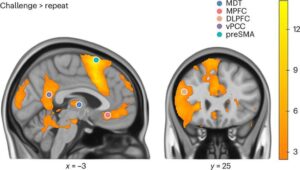

Powerful brain imaging has helped uncover why people with post-traumatic stress disorder (PTSD) who engage in negative self-talk may be struggling with the first line of treatment. The discovery, published in Nature Mental Health, sheds new light as to why underlying brain mechanisms mean some therapies potentially work for some people and not others, and could guide the development of more targeted treatments for PTSD.